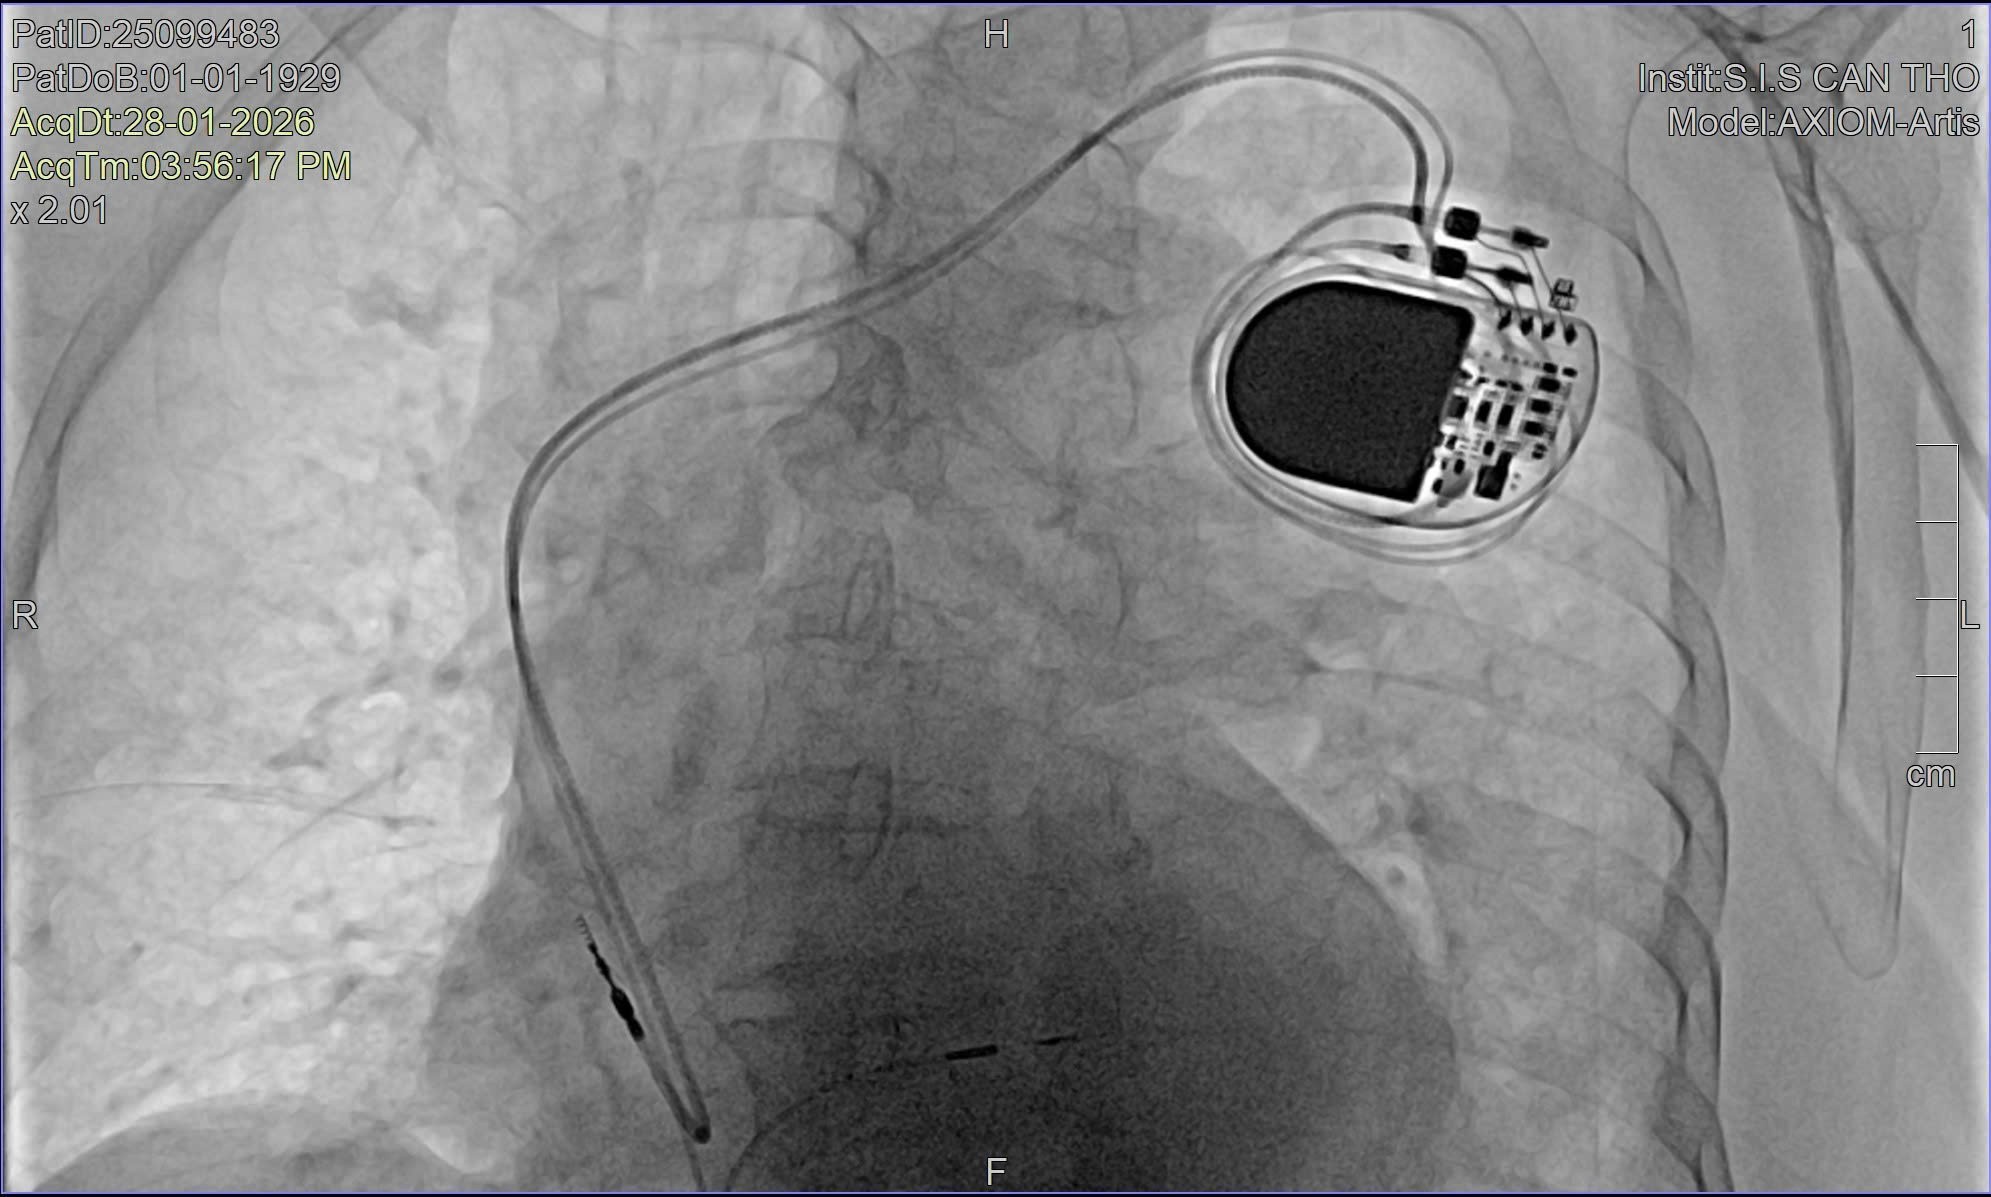

Theo BS.CKII Nguyễn Mạnh Cường – Phó khoa Nội Tổng hợp, Bệnh viện Đa khoa Quốc tế S.I.S Cần Thơ, do bệnh nhân tuổi cao và tình trạng rối loạn nhịp nghiêm trọng, ê-kíp điều trị đã đặt máy tạo nhịp tạm thời nhằm hỗ trợ nhịp tim và ổn định huyết động ban đầu. Song song đó, bệnh nhân được thực hiện các xét nghiệm chuyên sâu như xét nghiệm máu, chụp X-quang phổi và chụp mạch vành bằng DSA.

Kết quả chụp mạch vành cho thấy bệnh nhân có hẹp mạch vành mức độ vừa, phù hợp với độ tuổi và được điều trị nội khoa. Sau khi tình trạng toàn thân ổn định, các bác sĩ tiến hành hội chẩn và thống nhất chỉ định cấy máy tạo nhịp vĩnh viễn bằng kỹ thuật bó nhánh trái, phương pháp tiên tiến đang được triển khai tại Bệnh viện Đa khoa Quốc tế S.I.S Cần Thơ trong những năm gần đây.

Theo các bác sĩ, đây là trường hợp bệnh nhân lớn tuổi nhất từng được điều trị bằng kỹ thuật này tại bệnh viện, với nhiều thách thức do tuổi cao và rối loạn nhịp tim phức tạp. Hiện nay, tại Việt Nam, vẫn còn rất ít cơ sở y tế có thể thực hiện kỹ thuật cấy máy tạo nhịp bó nhánh trái, chủ yếu tập trung ở những bệnh viện có đầy đủ trang thiết bị hiện đại và đội ngũ bác sĩ chuyên sâu về điều trị rối loạn nhịp tim.

“Khác với phương pháp cấy máy tạo nhịp truyền thống, kỹ thuật cấy máy tạo nhịp bó nhánh trái giúp nhịp tim được dẫn truyền gần với sinh lý tự nhiên, bảo tồn chức năng co bóp của thất trái và giảm nguy cơ suy tim về lâu dài. Đặc biệt, phương pháp này mang lại nhiều lợi ích cho người cao tuổi khi vừa đảm bảo hiệu quả điều trị, vừa hạn chế biến chứng.” - BS. CKII Nguyễn Mạnh Cường cho biết.